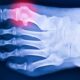

Cartiva toe implants are small cylindrical devices that are inserted into the joint space between the bones of the big toe. They are made of a hydrogel material that has a similar elasticity and compressibility as natural cartilage. The implant acts as a cushion and a spacer, reducing friction and inflammation in the joint. Cartiva toe implants are intended to preserve the natural motion of the toe, unlike other surgical options that fuse the joint or replace it with metal hardware.

People get Cartiva toe implants to relieve the pain and stiffness caused by toe arthritis. Toe arthritis is a degenerative condition that occurs when the cartilage that covers the ends of the bones in the toe joint wears away. This causes the bones to rub against each other, creating inflammation, swelling, and pain. Toe arthritis can also limit the range of motion of the toe, making it difficult to walk, run, or wear shoes. Some of the risk factors for toe arthritis are age, injury, genetics, and wearing high heels or tight shoes.